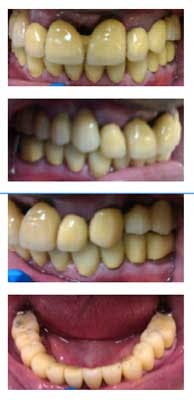

Fig. 6: Teeth prepared for PFMs

After preparing the teeth for full-coverage PFMs, the patient returns to the office to try in the metal copings. Copings fit appropriately and were sent back to the dental laboratory for porcelain bisque bake.

Fig. 8: Bisque bake